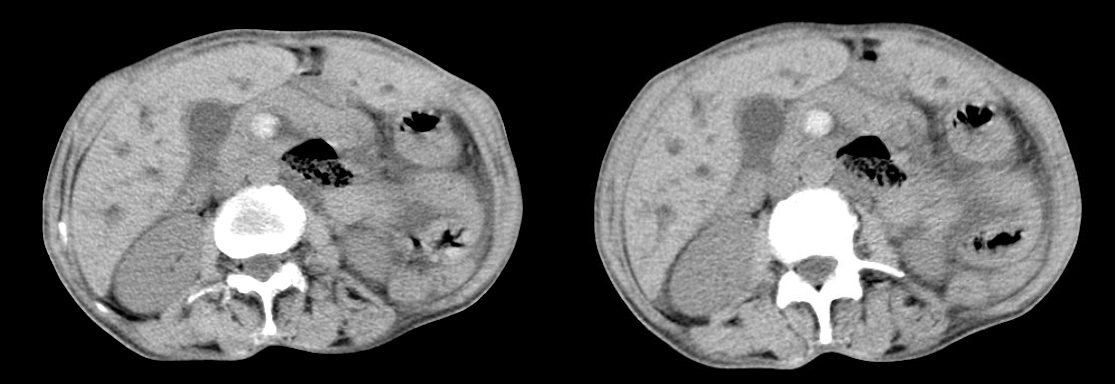

4、脂肪晕征

“脂肪晕”征的CT表现为肠壁与黏膜之间的环形低密度影,密度均匀,形态与肠腔相一致, CT值-10到- 68 Hu,厚度基本相等。发病部位以升结肠、横结肠、降结肠多见。出现伴随性肠周围脂肪聚集和肿大的淋巴结,则位于肠壁之外。黏膜下层脂肪聚集形成的环形结构称为“脂肪晕”征 ,它是慢性炎症性肠疾病 、细胞减数治疗或器官移植的急性表现。

小肠和/或结肠壁内出现脂肪曾经被认定为炎症性肠疾病,也可以说是Crohn′s病的征象。如果“脂肪晕”征在结肠出现同时伴有肠壁增厚则是溃疡性结肠炎的征象。但是目前有人提出,“脂肪晕”征也可以是正常表现。非炎症性肠疾病时出现“脂肪晕”征是正常的或是肥胖症。

肠腔中度扩张时可以更好地显示“脂肪晕”征 。但是,当肠腔扩张非常明显的时候,此征象则很少出现或消失,这可能是肠腔扩张肠壁紧张压迫脂肪层所致。清洁的肠腔自内向外可以形成气体—黏膜—脂肪晕—肠壁的结构层次,而非清洁肠腔则结构层次为肠内容物—脂肪晕—肠壁,因为黏膜与内容物混为一体。

左图:慢性溃疡性结肠炎横轴位CT图像:增厚的直肠壁表现为脂肪晕征,可见明显的直肠周围脂肪。

中图:溃疡性结肠炎CT图像:内环为粘膜层,外环为固有肌层,中间层为水肿的粘膜下层。

右图:克罗恩回结肠炎CT图像,显示回肠末端及盲肠增厚,伴有周围纤维脂肪增值。旁见一枚增大的淋巴结。

以上三图中,红箭头所指均系肠壁内脂肪。一般来说,肠壁脂肪的CT值应该在-10hu以下,但是由于部分容积效应,或同时并存的肠壁水肿,密度可能会较高。所以要注意“脂肪晕”征与水肿的鉴别:“脂肪晕”征的病理基础是黏膜下脂肪的聚集,而水肿是肠壁组织间隙水分的增多。所以,水肿以肠壁增厚为主,而“脂肪晕”征以黏膜与肠壁的分离为主。水的密度高于脂肪, CT值在0 Hu左右。另外,水肿是某种疾病的急性反应并有相应的临床症状,而“脂肪晕”征的患者是无胃肠道症状的。

“脂肪晕”征、Crohn′s病、肾结石、肥胖症之间的关系 Crohn′s病与“脂肪晕”征的共性是都有脂肪晕。Crohn′s病的脂肪晕程度小于“脂肪晕”征且常伴有黏膜紊乱、肠壁增厚、肠腔狭窄等变化而单纯“脂肪晕”征没有。有人报告 Crohn′s病患者中肾结石呈高发状态,说明了Crohn′s与肾结石的关系。肠壁“脂肪晕”征是炎症性肠疾病的表现之一,但可以在没有炎症性肠疾病时出现,此时代表正常表现或肥胖症。